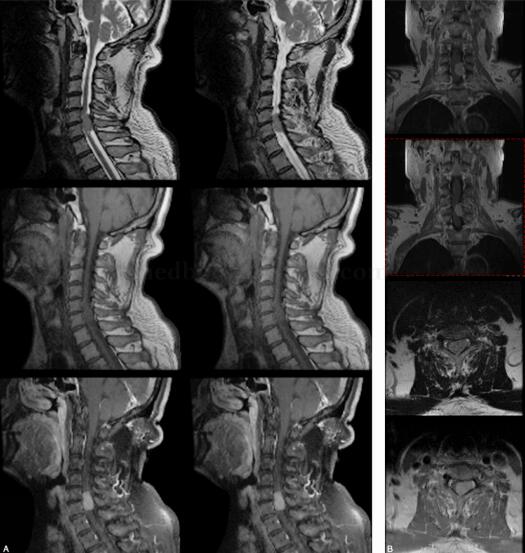

患者男,69岁,3年前无明显诱因出现左侧上肢麻木、疼痛,当地医院按心脏疾病治疗,未好转。2010年10月进展为左侧上下肢麻木、活动不灵,当地医院诊断为脑血栓。2011年1月患者出现右侧肢体活动不灵,不能独立行走。患者为求进一步诊治入我院。病来饮食、睡眠可,便秘,小便正常(图1)。

图1 颈椎序列整齐、曲度正常;颈3~7间盘向后隆起,颈4~7黄韧带肥厚。颈5~6椎体水平椎管内见等信号占位,大小约18.1mm×13.5mm×24.3mm,脊髓受压右移。增强占位呈均匀明显强化